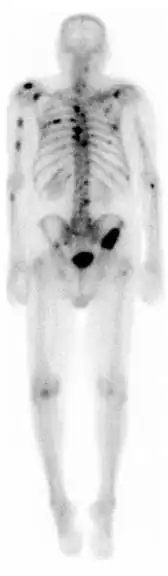

Bone scintigraphy

A nuclear medicine whole-body bone scan. The nuclear medicine whole-body bone scan is generally used in evaluations of various bone-related pathology, such as for bone pain, stress fracture, nonmalignant bone lesions, bone infections, or the spread of cancer to the bone. | |

A bone scan or bone scintigraphy /sɪnˈtɪɡrəfi/ is a nuclear medicine imaging technique used to help diagnose and assess different bone diseases. These include cancer of the bone or metastasis, location of bone inflammation and fractures (that may not be visible in traditional X-ray images), and bone infection (osteomyelitis).[1]

Nuclear medicine provides functional imaging and allows visualisation of bone metabolism or bone remodeling, which most other imaging techniques (such as X-ray computed tomography, CT) cannot.[2][3] Bone scintigraphy competes with positron emission tomography (PET) for imaging of abnormal metabolism in bones, but is considerably less expensive.[4] Bone scintigraphy has higher sensitivity but lower specificity than CT or MRI for diagnosis of scaphoid fractures following negative plain radiography.[5]